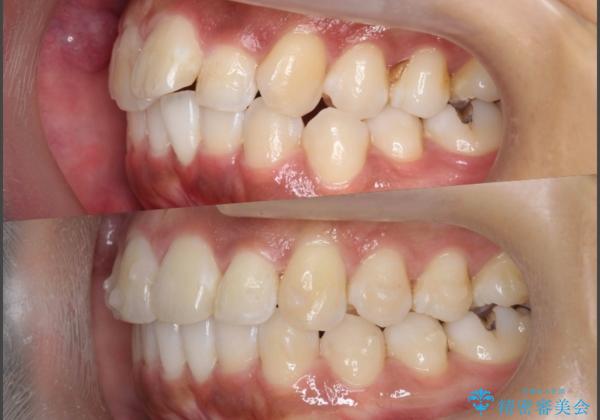

出っ歯感のある前歯を治したい、抜歯をしないマウスピース矯正

- 前歯のガタつき、突出感のある前歯の改善を求めて来院されました。

前歯の角度を改善し審美性を高めるとともに、奥歯のガタつきも並べ直すことで安定した咬合関係の確立を目指します。

歯列の側方拡大をしっかりと行ったことで歯を抜かずに前歯の角度をしっかりと改善することができました。